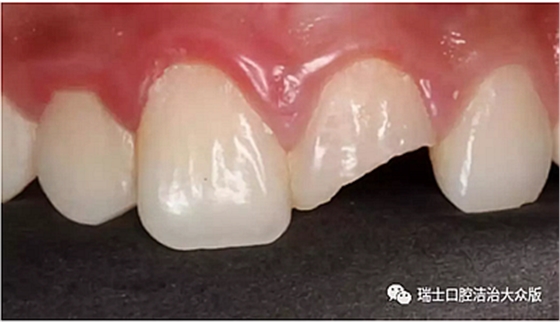

1、冠折(圖4)

成人牙齒外傷了怎么應急處理?

圖4. 冠折

如果折斷的范圍局限于牙釉質可能沒有明顯的癥狀,但如果折斷至牙本質甚至牙髓,就會出現(xiàn)牙齒的敏感和疼痛。此時不論折斷范圍如何,均可將折斷的部分找回,帶至醫(yī)生處就診,同時避免冷熱刺激和進食刺激性食物。